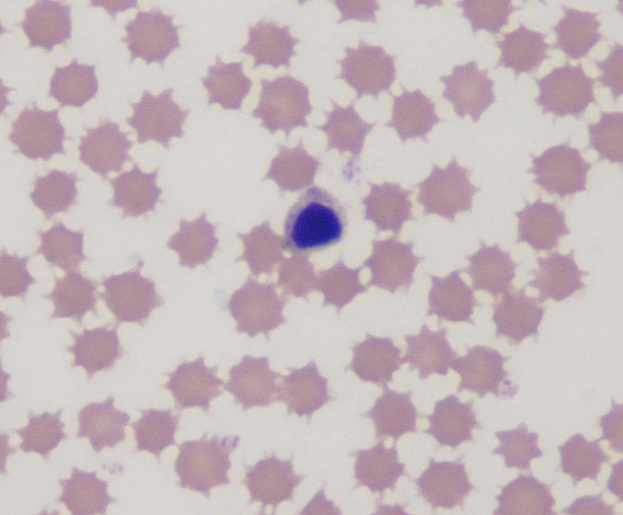

Echinocytic RBCs

cow